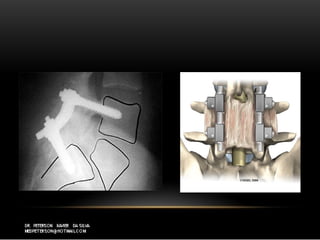

CirurgiaCirurgia

 Artrodese com parafusos pelicularesArtrodese com parafusos peliculares

 Plif ou AlifPlif ou Alif

 Laminectomia descompressiva + artrodeseLaminectomia descompressiva + artrodese

 Discectomia + artrodeseDiscectomia + artrodese

CirurgiaCirurgia  Artrodese comparafusos pelicularesArtrodese com parafusos peliculares  Plif ou AlifPlif ou Alif  Laminectomia descompressiva + artrodeseLaminectomia descompressiva + artrodese  Discectomia + artrodeseDiscectomia + artrodese